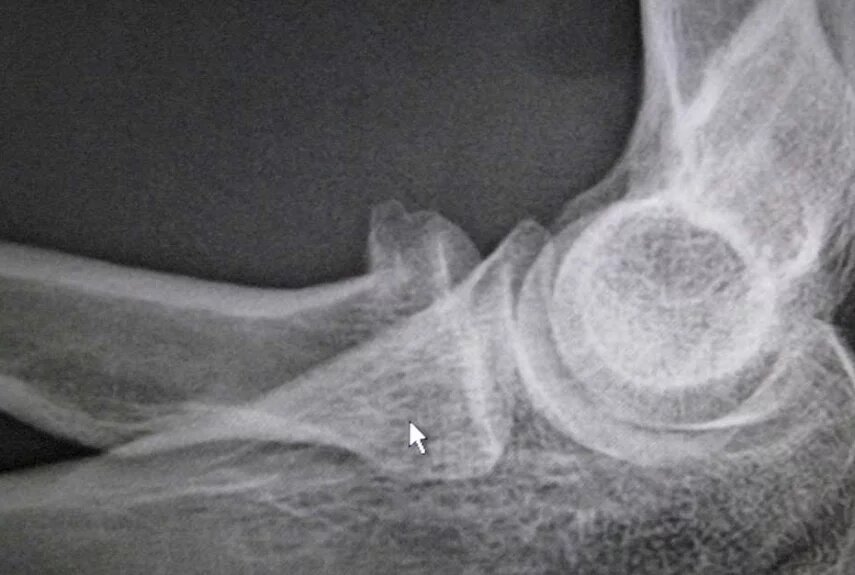

1. Занятие армрестлингом

«Безопасный», казалось бы, вид спорта грозит переломами плечевых костей со смещением осколков. Пострадавшего приходится срочно госпитализировать, чтобы сделать операцию и зафиксировать костные отломки металлическими пластинами.

Когда скручивающая нагрузка на руку достигает пика, кость ломается. Какой бы крепкой и здоровой она ни была. Если у спортсмена мощные мышцы, они усугубляют ситуацию — еще сильнее давят на кость.